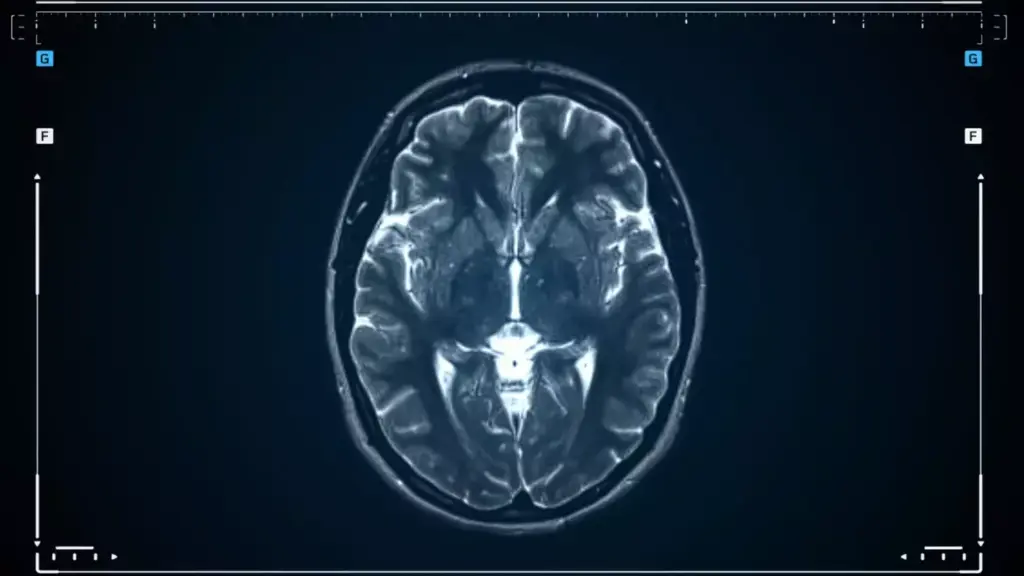

1. MRI (Magnetic Resonance Imaging): Gives detailed brain images, helping spot tumors.